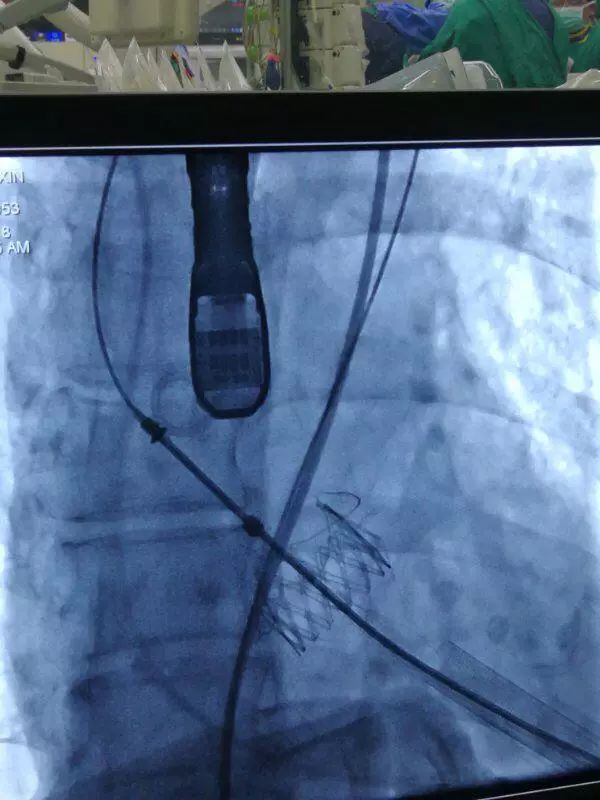

术中,在TAVI心脏手术团队的协作下,首先在患者心尖部位开一小孔,然后操控一根细长的输送鞘,将人工生物心脏瓣膜送入患者心腔。在造影屏幕监视下,新瓣膜被准确定位和放置于病变主动脉瓣位置。原来的心脏泵血“阀门”因关不紧“漏水”,新瓣膜“安装”完毕后,就像一扇运行良好的新“阀门”,一张一合地开始工作了。

造影评估主动脉根部结构

人工瓣膜释放